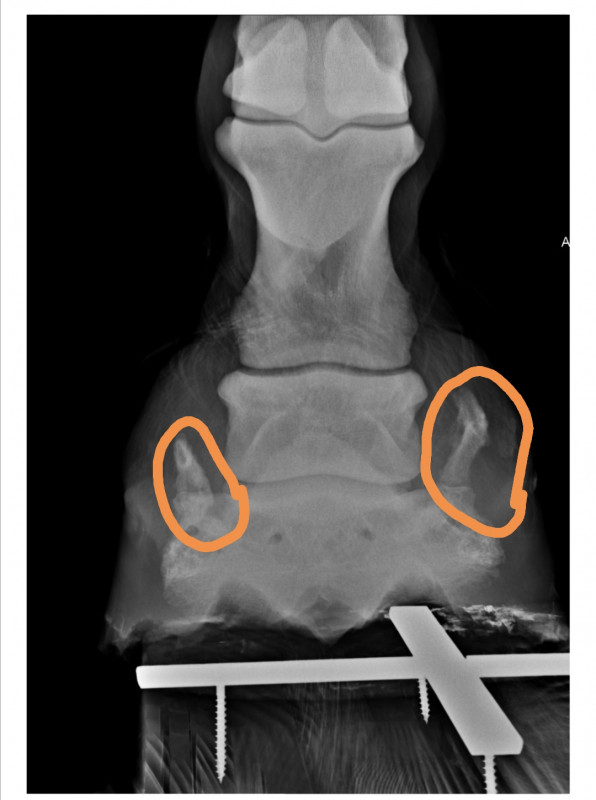

argamelle Alors le mien cumule 2 choses : arthrose et ossification des cartilages dans le pied. Et ce sont les ossifications, à priori, qui m'ont poussé à faire les radios et découvrir l'arthrose.

Radios du pied donc qui montre l'arthrose et l'ossification.

Mais en Septembre on part en rando et je le sens vraiment pas bien. Donc retour maison plus tôt que prévu et radio des deux pieds : l'ossification est toujours là et l'arthrose s'est amplifiée.

Bref en gros les boiteries sur le cercle seraient plutôt liées à l'ossification et le fait qu'il trébuche à l'arthrose qui se trouve sur la face antérieur du pied et qui agit donc sur la levée et l'avancée du pied.

Je vais chercher les photos des radios

J'ai entouré les ossifications. Quand il fait des cercles serrés ou qu'il est en terrain instable qui le fait basculer le pied latéralement, les cornes que font les ossifications "rentrent" et vont titiller la phalange au dessus... Et l'arthrose sur le devant...

Édité par pollux77 le 06-05-2020 à 16h55